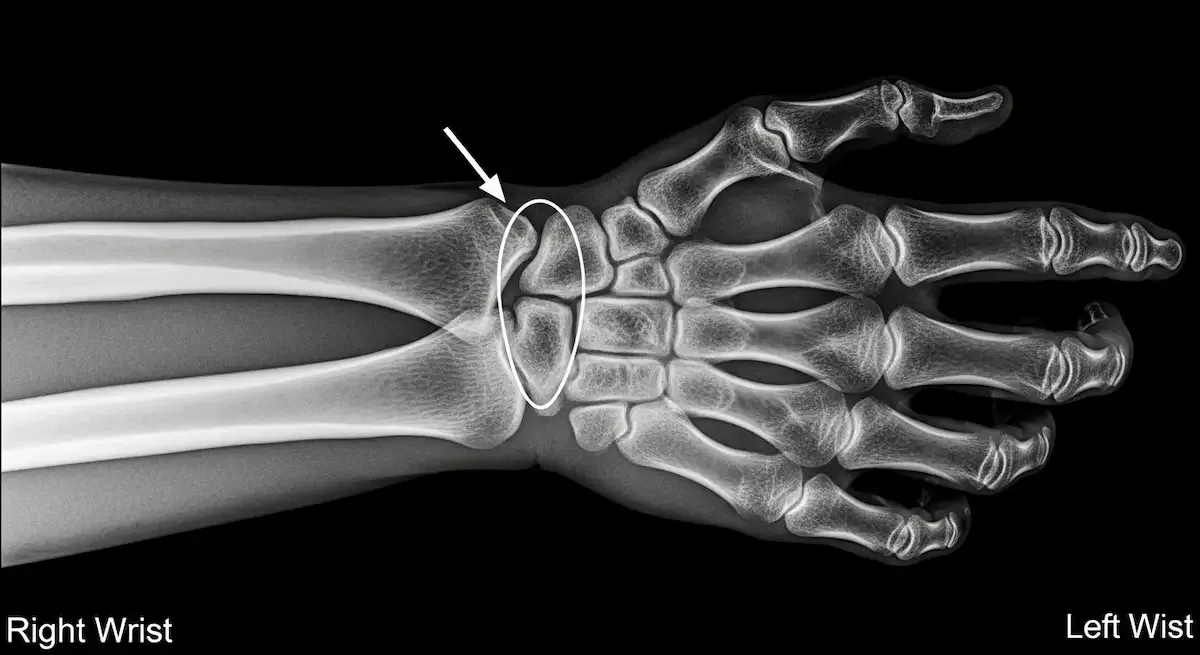

A Síndrome do Canal de Guyon é uma neuropatia compressiva do nervo ulnar no punho. O canal é formado por ossos do carpo e ligamentos, conduzindo o nervo e a artéria ulnar até a mão.

Fraturas, artrose do carpo, cistos sinoviais e tumores benignos também estreitam o canal.

O diagnóstico da Síndrome do Canal de Guyon começa pela história clínica e exame físico com testes de provocação e digitopercussão sobre o canal.

- A ultrassonografia detecta espessamento do nervo e pesquisa cistos.

- Radiografias avaliam fraturas e artrose.